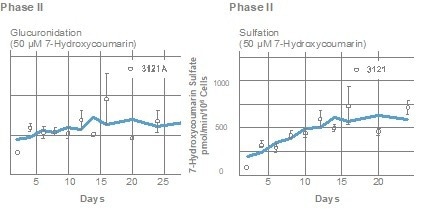

Metabolizing enzyme activity

In human HEPATOPAC cultures, activities of various CYP and Phase 2 enzymes were observed, with metabolites being analyzed through mass spectrometry. The following graphs demonstrate that HEPATOPAC co-cultures sustain their metabolic functions over an extended period.

Image Credit: BioIVT